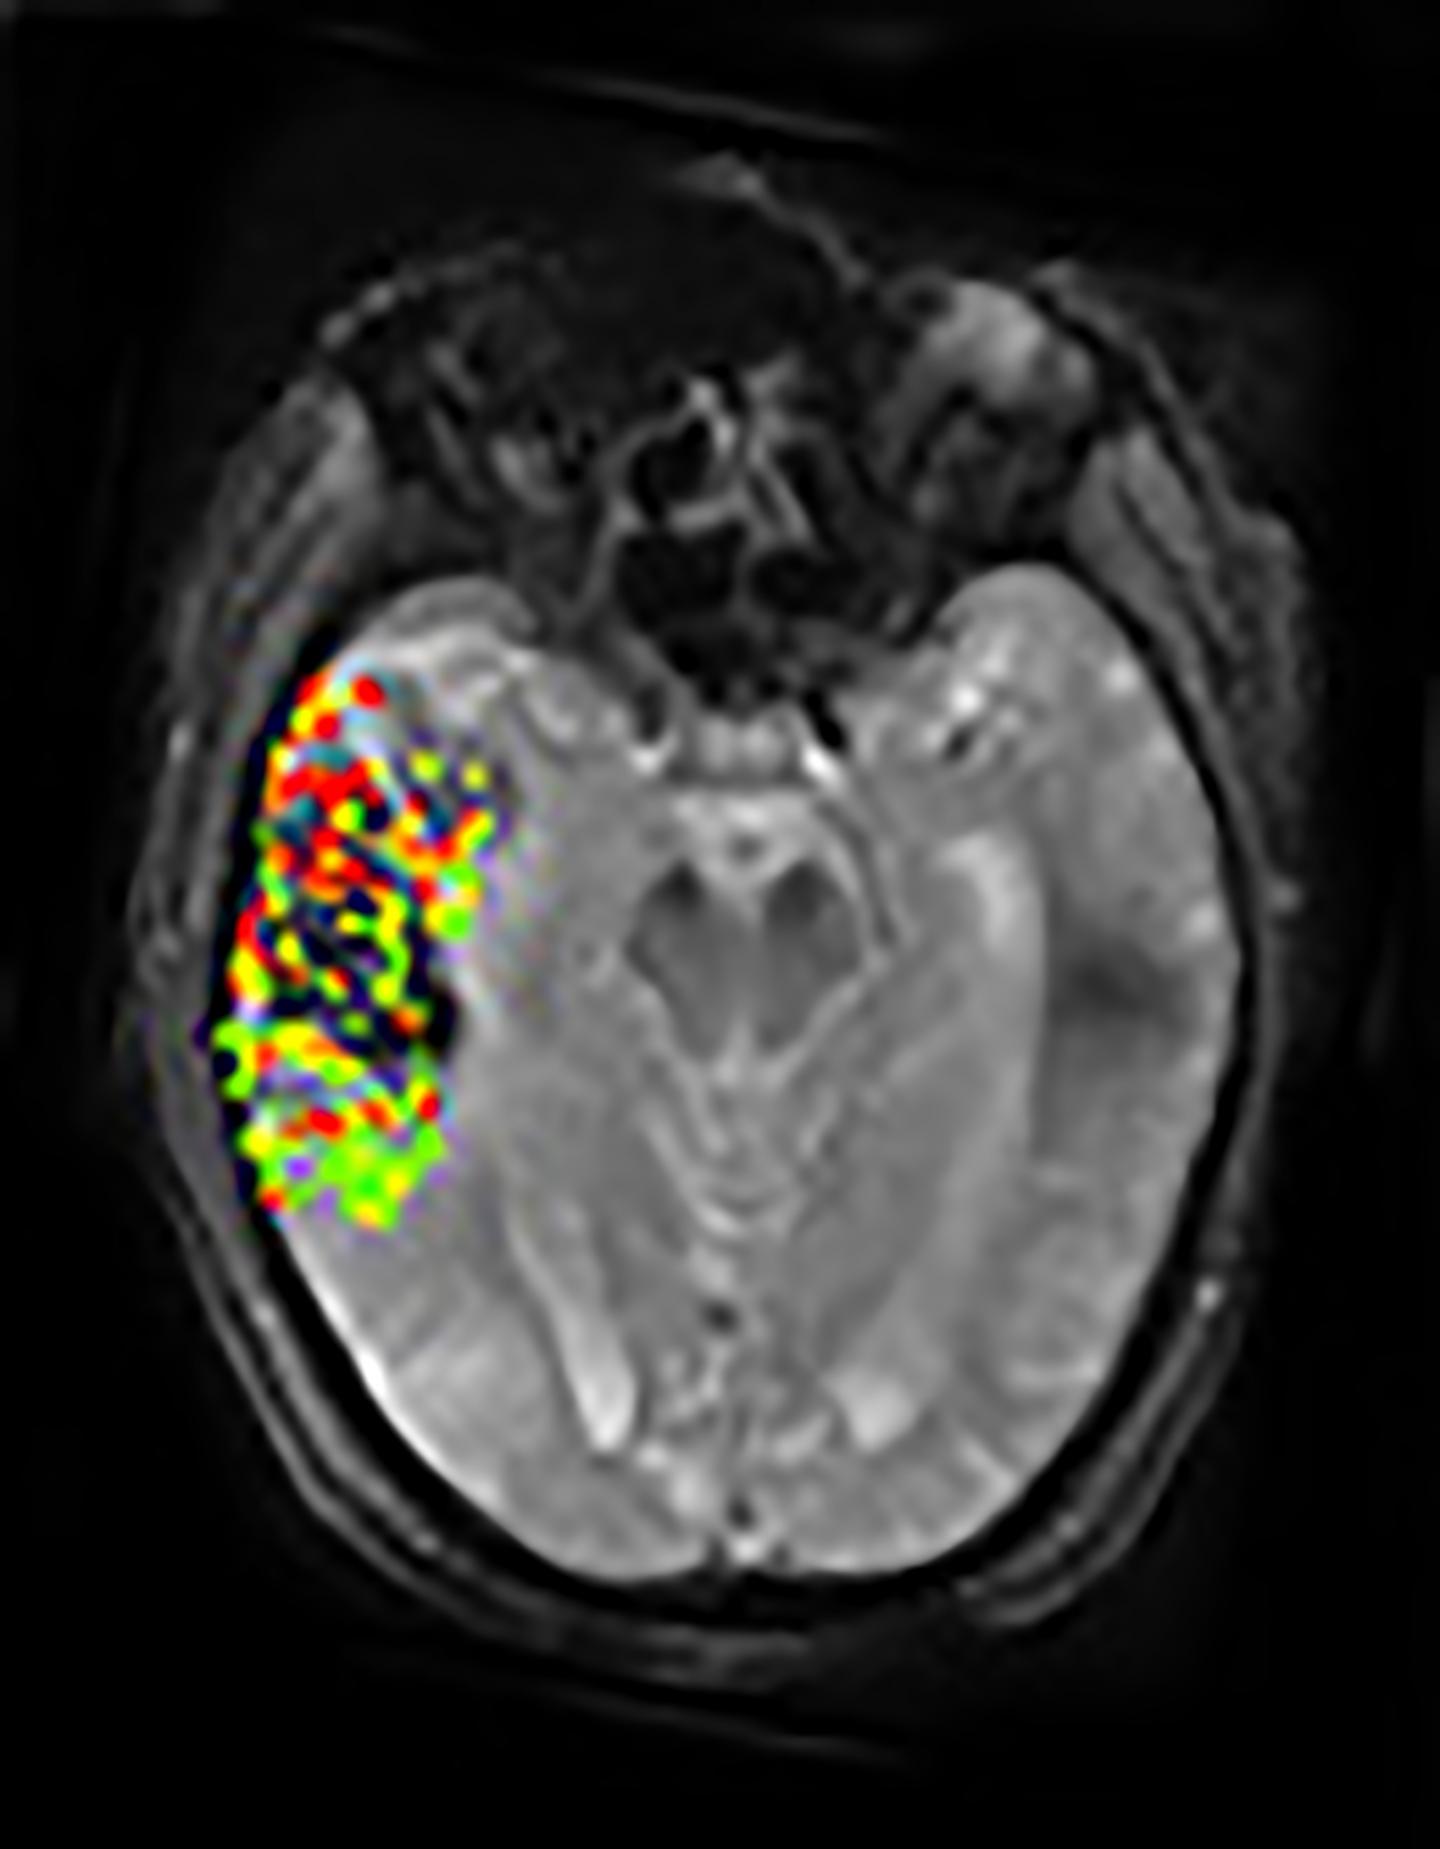

In a study of stroke patients, investigators confirmed through MRI brain scans that there was an association between the extent of disruption to the brain's protective blood-brain barrier and the severity of bleeding following invasive stroke therapy. The results of the National Institutes of Health-funded study were published in Neurology .

Using a new method of image processing, Dr. Leigh's group was able to get detailed measurements on the extent to which the blood-brain barrier is disrupted following a stroke. Combining that data with findings from the DEFUSE-2 study revealed that large degrees of blood-brain barrier disruption were associated with severe bleeding following endovascular therapy. Extensive breakdown of the blood-brain barrier was associated with parenchymal hematoma, a form of bleeding in the brain that carries the greatest risk for the patient. In addition, the results showed a link between the location of blood-brain barrier damage and post-treatment brain bleeding.

According to the authors, examining blood-brain barrier disruption on brain images may potentially help doctors identify patients not likely to benefit from endovascular therapy. "It is too early to say how these images will be able to help guide clinical decisions, but they can expand how we think about stroke, especially as we try to broaden treatment options for this disease that can have devastating consequences," said Dr. Leigh.